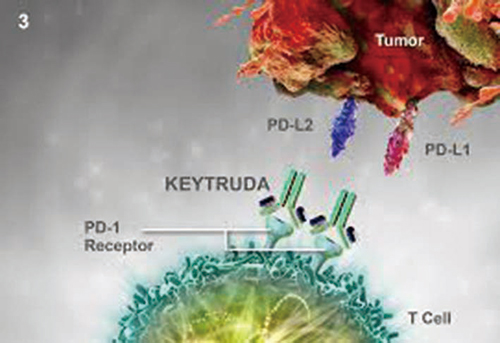

K药肺癌适应证获批

K药肺癌适应证获批

2019-04-02 11:31:22

3月28日,国家药品监督管理局(NMPA)官网显示,PD-1免疫检查点抑制剂帕博利珠单抗(商品名:可瑞达,国内俗称“K药”)联合培美曲塞和铂类化疗药物一线治疗表皮生长因子受体(E…